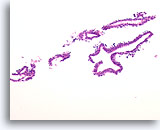

Papillair carcinoom, Borst FNA, Celblok.

Een immunokleuring met p63 voor myoepitheliale cellen is ook negatief bij de patiënt die in voorgaande afbeeldingen getoond is; dit steunt de diagnose van papillair carcinoom.

Papillair carcinoom, Borst FNA, Celblok.

Een immunokleuring met p63 voor myoepitheliale cellen is ook negatief bij de patiënt die in voorgaande afbeeldingen getoond is; dit steunt de diagnose van papillair carcinoom.